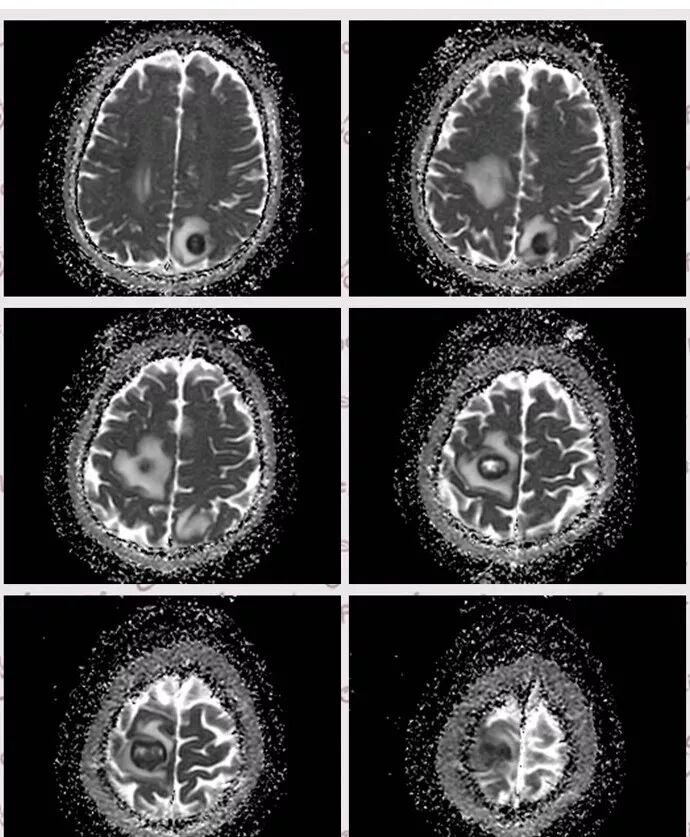

右肺下叶见不规则软组织影,边缘不清,内夹杂气体,背段支气管未见明显阻断,增强扫描下叶病灶内见类圆形低强化区,其边缘光滑,见低强化区壁,颅脑左侧枕叶及双侧顶叶见多发长T1长T2信号,T2高信号内见类圆形异常信号,壁呈低信号,DWI环形壁未弥散受限,内容物弥散受限,周围为水肿区,增强扫描呈多发环形强化,考虑血源型感染,颅内及右肺下叶脓肿形成

脑内右侧顶叶病灶与其它脑内病灶不一致,壁弥散受限,内容物弥散低信号,转移瘤不能排除,其它脑内病灶支持脑脓肿

多数薄壁,脓腔弥散受限是典型脑脓肿;右侧额叶的厚壁,壁受限,表现跟其他完全不一样,很是疑惑

颅内部分病灶是环形受限,中心没有受限,不支持脓肿

脑部病灶DWI受限,脓肿,中间也有受限,DWI第一,第二张图都是中间受限,第三,四是周围受限

今天这个颅脑病灶需要转移和脓肿鉴别,转移和脓肿都可以这样环形强化,但是脓肿是中心弥散受限,脓肿壁弥散不受限,转移和脓肿弥散正好相反,转移是环壁弥散受限,中心坏死区弥散不受限。

DWI值对鉴别脑脓肿与囊性脑转移瘤有重要意义。包膜期脑脓肿其内容物主要为炎症细胞、微生物及蛋白质,其黏稠度相对较高,水分子弥散受到限制,DWI表现为均匀高信号。转移瘤囊变区主要以浆液性坏死物为主,其黏稠度相对较低,水分子扩散速度相对较快,DWI表现为低信号

脑脓肿和囊性脑转移瘤的鉴别点就是粘液(结合水)浆液(自由水)的鉴别

下图是例举其他病例:

颅内环形的高信号,但是可以发现这个的DWI环是厚的,但是增强扫描的环是非常薄的,如果是肿瘤的,就是壁的弥散受限是肿瘤细胞的话,那么他强化的环应该跟DWI的环的厚度是一样的,所以这个环形的低DWI高信号应该是脓肿。而且就是关于这个脓腔壁的,就是脓腔的外壁是非常模糊的,而内壁还是相对光整,环不是很完整。下面一个图,没有给到,DWI上可以看到沿着破溃的脓肿壁向外侵出去的感觉,如果是环形转移的,那么它的那个内壁是更加不光整,而外壁是相对比较清楚一些的。

这个颅内病灶增强扫描的无强化区范围与DWI高信号范围是一致的,所以还是脓腔内受限,至少时期不那么典型,不是纯粹的高信号,DWI是厚层、增强是薄层;而且扫描角度也不一样,所以无法完全对上

脓肿内的坏死、脓液形成也不是一次性完全形成的,就像在肝脓肿内,信号也是不一致的。重点还是在于强化区的地方弥散受限了还是无强化区的地方受限了,还是那句话,强化壁比弥散壁薄很多,无强化区比弥散不受限区范围大多了